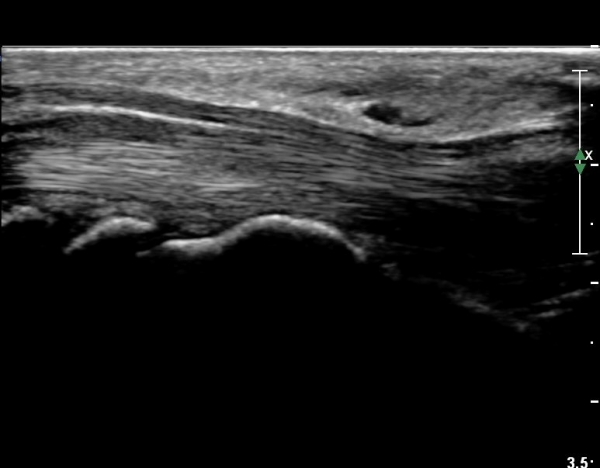

¼Õ¸ñ°ú ¼ö±Ù°ü±ÙÀ§ºÎ Ⱦ´Ü¸é°Ë»ç¿¡¼­  ÈûÁÙÀÇ ºñÈÄ¿Í ÈûÁÙ ÁÖÀ§ Ȱ¾×¸· ºñÈİ¡ °üÂûµÇ³ª

Á¤Áß½Å°æ ºÎÁ¾Àº °üÂûµÇÁö ¾Ê´Â´Ù(»çÁø 3, 4).